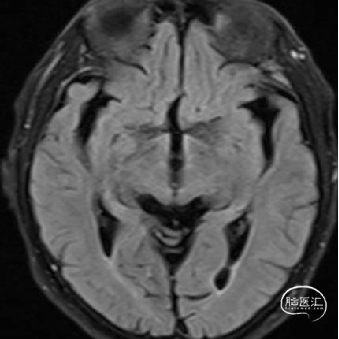

头部DWI、Flair